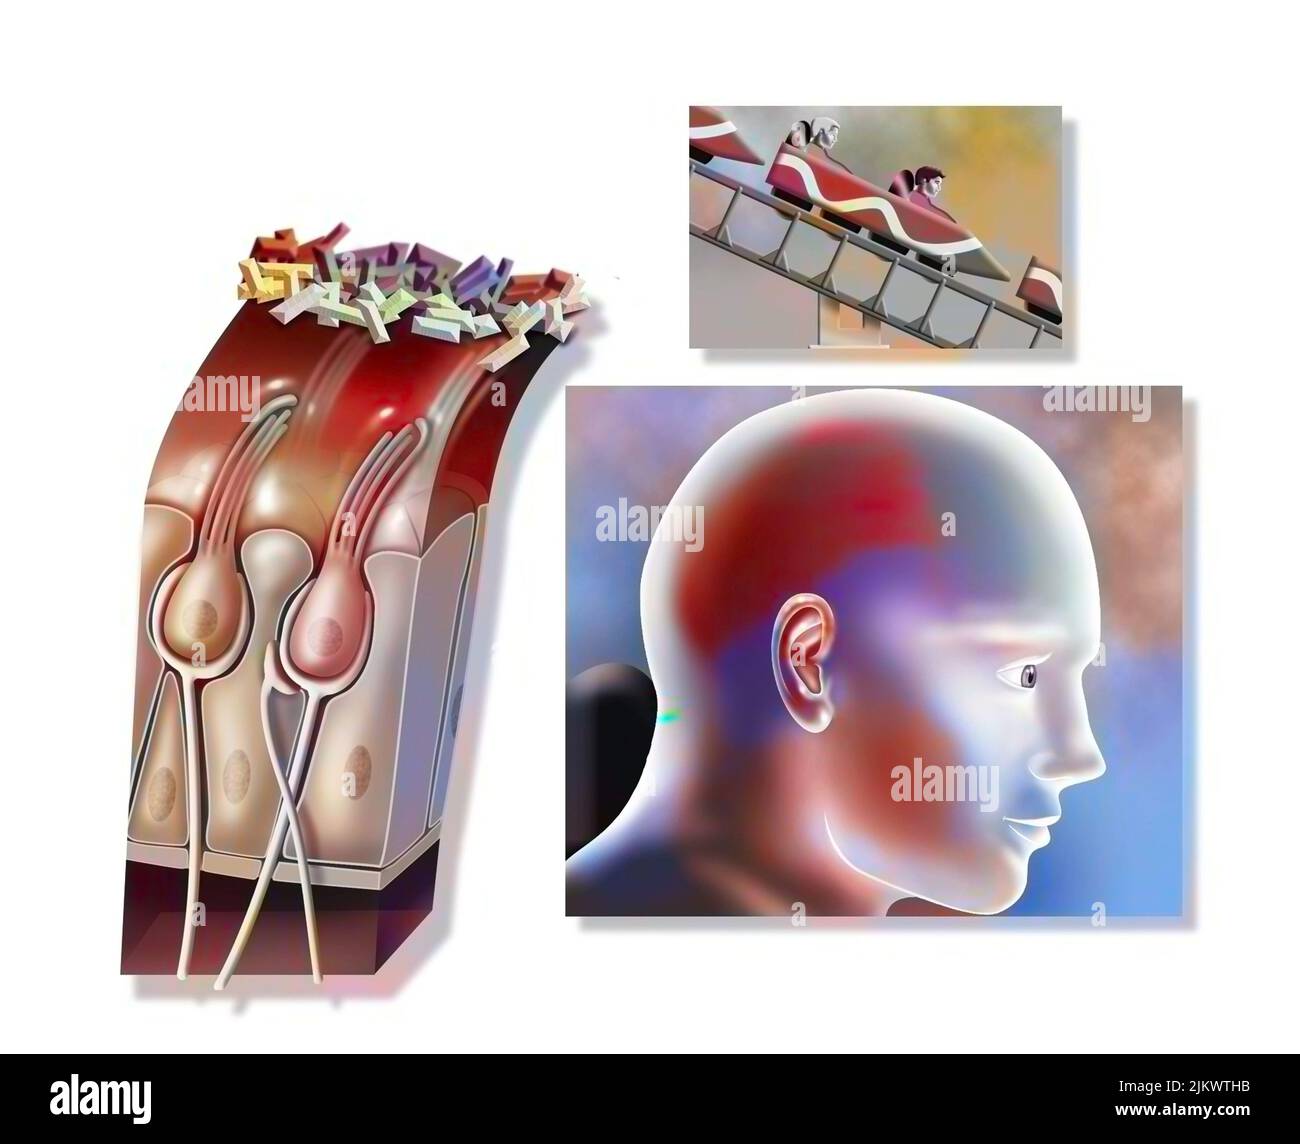

RF2JKWRF2–Pla (potentialisation à long terme) après une semaine, étape 2 : la synapse est stimulée avec une plus grande efficacité.